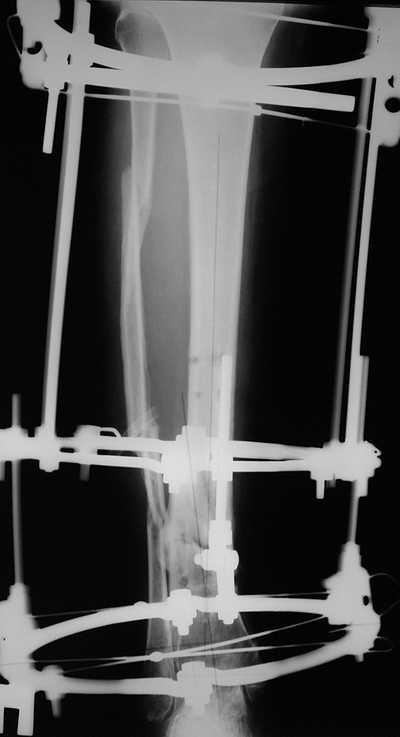

Male 54 years old, diabetic, blind in both eyes, with infected (MRSA) non union distal tibia after fracture 8 month ago. In acute phase treated by ORIF with LCP tibia and fibula. Treatment complicated by infection and after 6 month hardware was removed and treatment continued by cast fixation. You can see malposition of fragments In this stage beginning treated by Ilizarov fixation with use Hexapod system, allows anatomical position of fragments and you see signs of union.

Sorry, I wiil tray now pictures of my case.